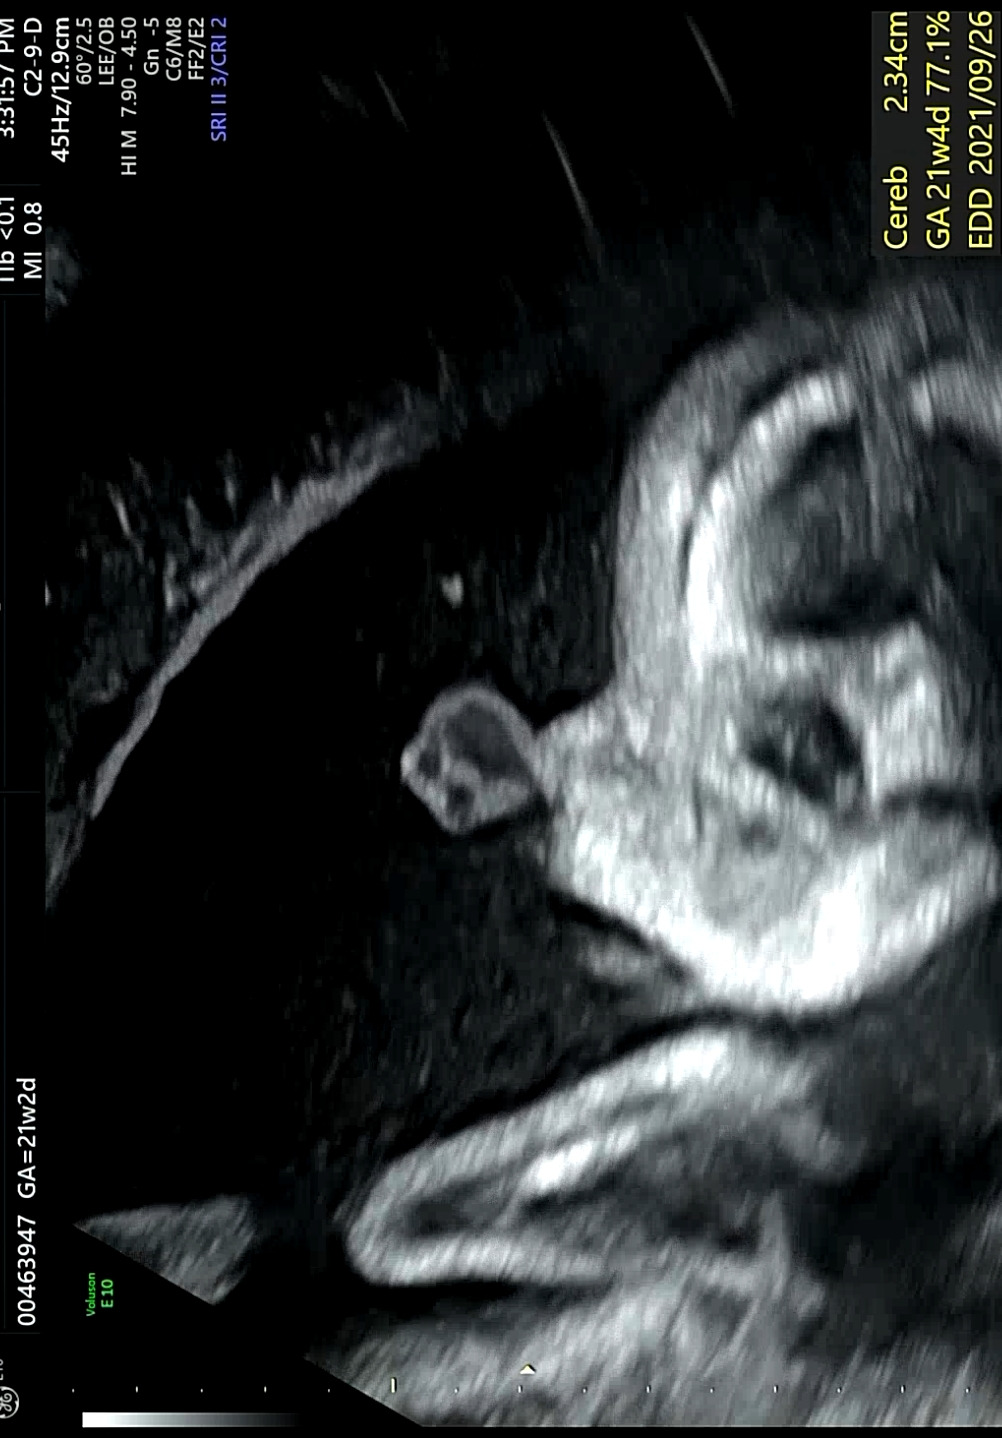

21주 : 심장 두근거림 증상...

가끔씩 누워있을 때 심장에 통증이 생기면서 두근거림이 크게 느껴지는 증상이 생겼다. 그래서 정밀초음파검사 때 의사에게 말하니 심전도 검사를 해보자고 하여 했고, 별 이상은 없었다. 임신중독증 상일 수 있으니 혈압측정기기를 구입해서 매일 체크하라고 해서 막달까지 매일 측정했으나 정상이었다. 아마도 자궁이 커지면서 장기들이 위로 밀리다 보니 심장에 영향을 준 것 같다.